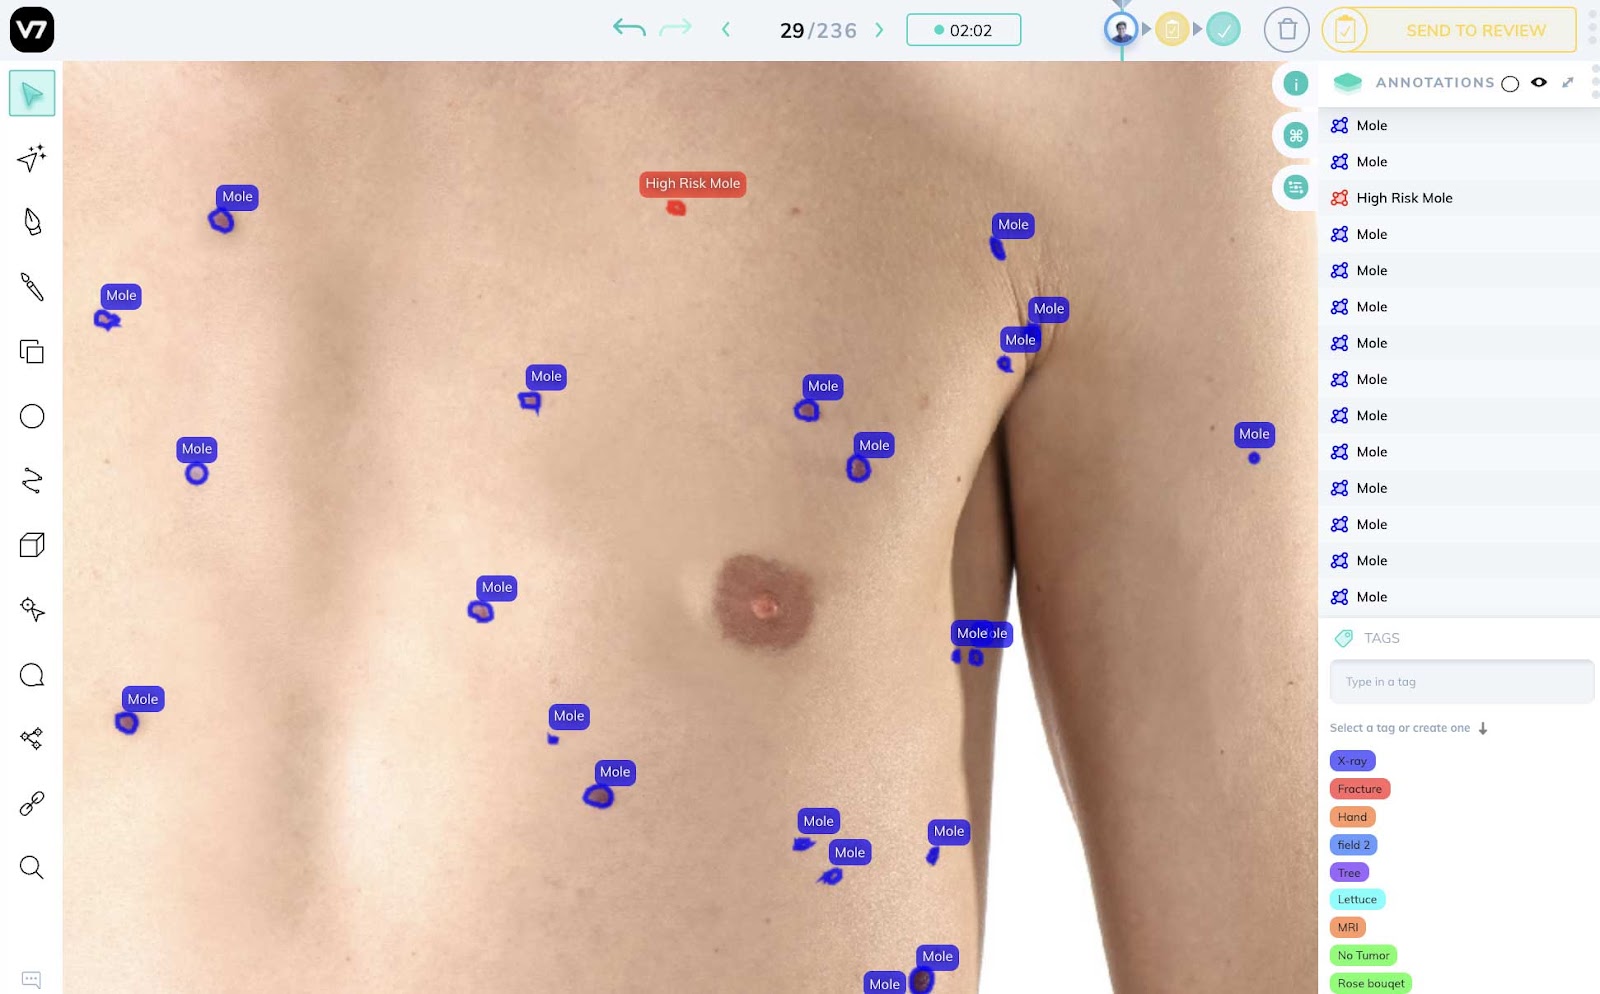

癌症检测

图像识别允许医生通过比较图像中的癌细胞和非癌细胞来识别异常和变化。

自动检测允许使用来自磁共振成像 (MRI) 扫描的数据更快地诊断癌症。计算机视觉已经成功应用于乳腺癌和皮肤癌的检测。

这是一个带注释的痣的示例,可以对其进行分析以在早期检测黑色素瘤皮肤癌。